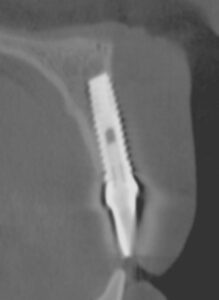

This article focuses on an alarming issue of implants loosing support and integration due to excessive soft tissue pull or tension from a shallow vestibule and/or dense frenum pull. We now have an abundant number of cases that exhibit tissue recession and possibly late loss failure. For example, Figures 1A-1C show a case of late implant failure. In 1996, the patient received

an implant on tooth No. 8. The immediate result was very good, both functionally and aesthetically (Figure 1A). However, the 2007 follow-up visit revealed severe gingival recession (Figure 1B depicts the recession and distinct frenum pulls). The cross-sectional image from 2007 (Figure 1C) demonstrates the lack of bone in the facial and apical aspects of the implant. The presence of frenum pulls (evident in Figure 1A from 1996) should have been a reason for concern. We believe that a prophylactic release of the frenum pull prior to implant loading would have prevented such outcome. Today, we would have addressed the frenum pull with a CO2 frenectomy prior to implant loading.

Figure 2 demonstrates two single Brånemark implants placed nearly 15 years prior. Natural buccal and lingual narrowing of the alveolar ridge and high mucogingival junction combined with frenum pull could possibly contribute to the buccal gingival recession and, consequently, the implant failure. In this case, the patient could have benefited from the tissue tension release.